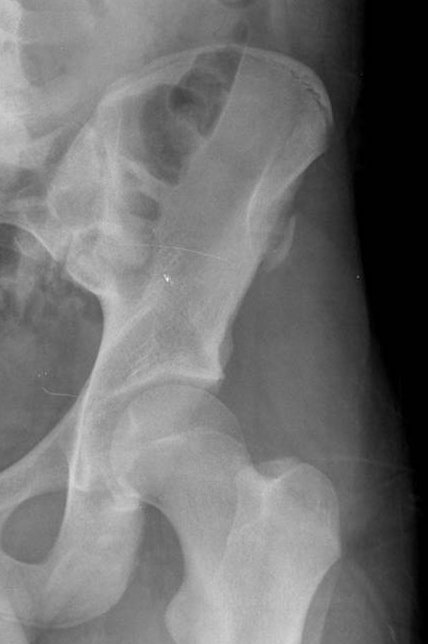

Anterior-Superior Iliac Spine Avulsion

This is the attachment of the sartorius and tensor fascia lata muscles.